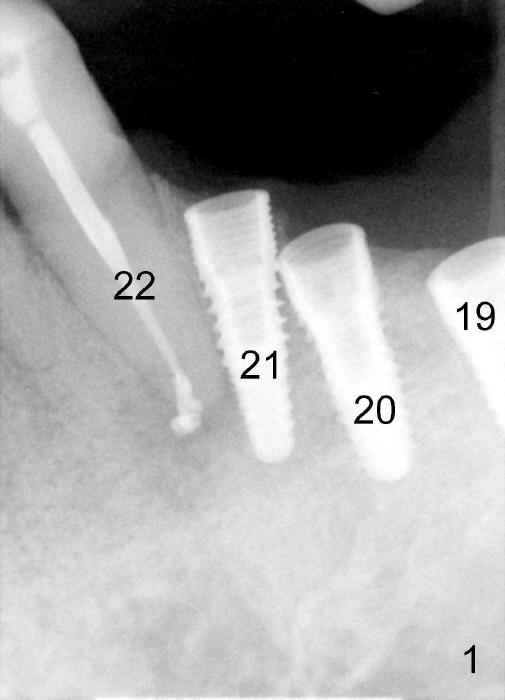

Three weeks post RCT for #22, the patient returns for implant placement at the sites of #19-21 (Fig.1,2). He is asymptomatic. But pain is not well controlled when osteotomy is being done at the site of 21. A shorter and smaller implant (4.1x12 mm, insertion torque <15 Ncm) is placed than planned (4.5x14 mm). One month postop, the implant is not stable at the site of 21 (Fig.3-5). There is a space around the implant, which is continuous with periapical radiolucency (Fig.3 arrowheads). It appears that the immediate implant should have been placed longer following RCT of the neighboring tooth. The tooth #21 has also pre-existing periapical infection.